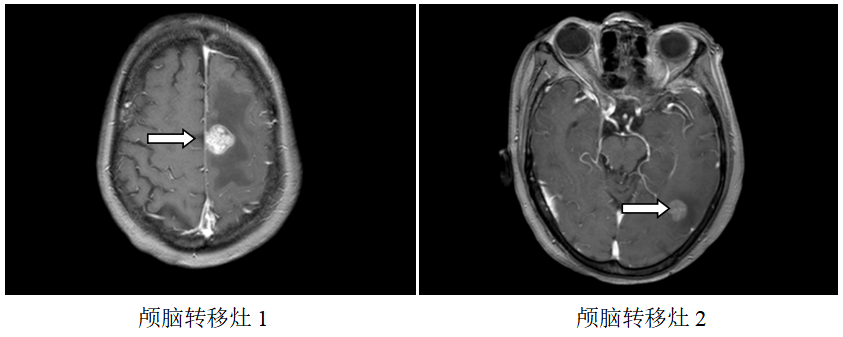

颅脑MR:左侧额、枕叶脑转移瘤;

局部放疗:2019.7.23~2019.8.7予脑转移灶调强放疗DT3900CGy/13F。

再次放疗:2020.06.04复查颅脑MR:原左侧额、枕叶脑转移瘤较前缩小,右侧颞叶新增转移瘤,于2020.6.15-6.26予脑转移灶调强放疗DT3000CGy/10F。

继续维持治疗:新增右侧颞叶脑转移灶,配合脑转移局部放疗,其余病灶好转,继续原方案全身治疗。